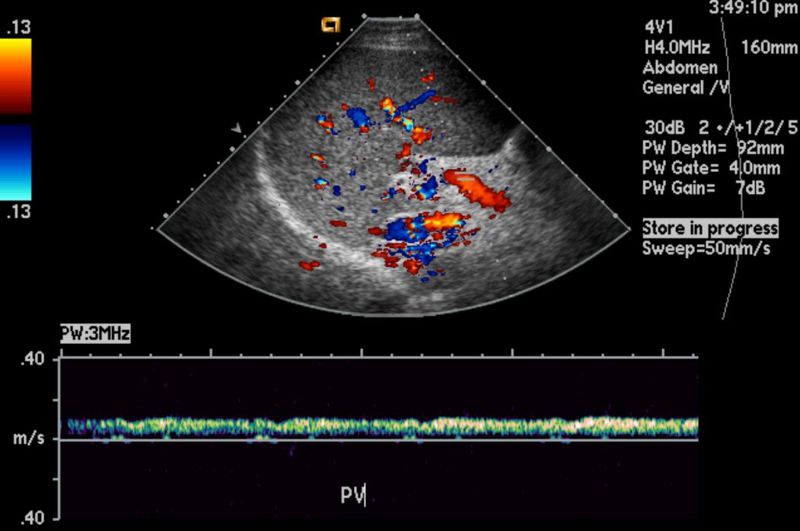

El ultrasonido hepatobiliar permite la detección de anormalidades estructurales en el hígado y las vías biliares de los niños. Esto incluye la identificación de cambios en el tamaño, la forma y la ecogenicidad del hígado, así como la presencia de lesiones focales como quistes, tumores y anomalías vasculares.

La evaluación de la fibrosis hepática es crucial en el manejo de las enfermedades hepáticas crónicas en niños. El ultrasonido hepatobiliar puede proporcionar información útil sobre la presencia y la gravedad de la fibrosis hepática mediante la identificación de signos indirectos, como engrosamiento de las paredes de los conductos biliares, irregularidades en la superficie hepática y cambios en la ecogenicidad del parénquima hepático.

Además de las enfermedades hepáticas crónicas, el ultrasonido hepatobiliar también puede ayudar a diferenciar otras patologías abdominales en niños. La identificación de hallazgos específicos, como la presencia de cálculos biliares, dilatación de la vía biliar o ascitis, puede orientar el diagnóstico diferencial y guiar la evaluación adicional.